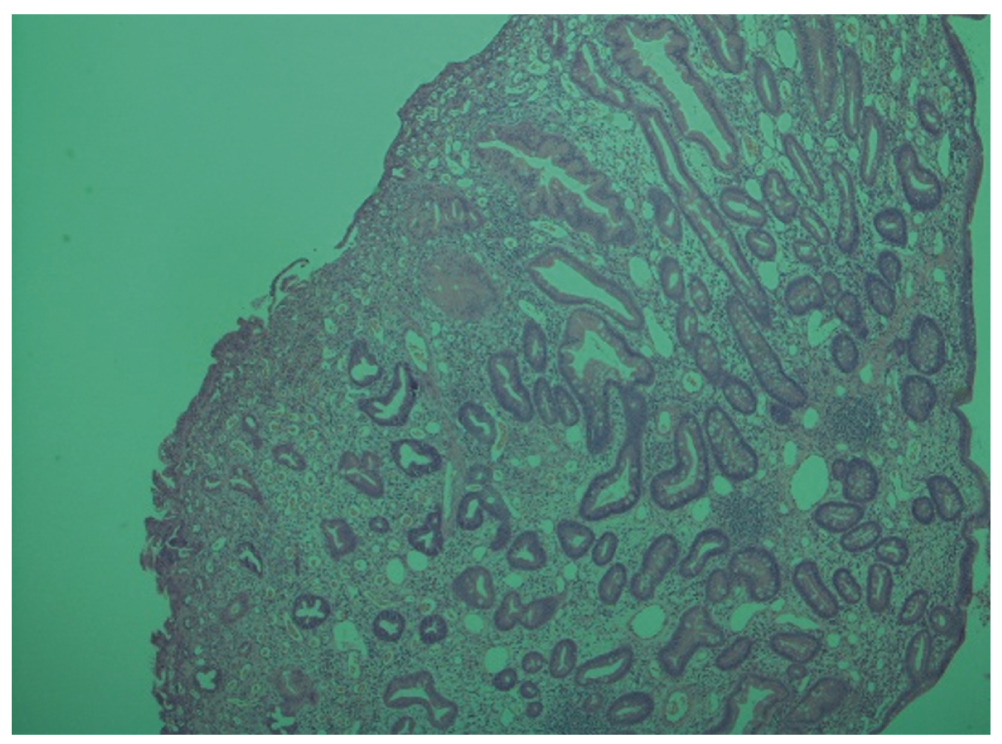

По данным гистологического заключения удалённое новообразование представляет собой полиповидный фрагмент слизистой оболочки толстокишечного типа с кистозно-расширенными железами неправильной формы, в просвете которого имеется обильный воспалительный экссудат. Собственная пластинка расширена, со смешанно-клеточной инфильтрацией и участками грануляционной ткани. Указанные изменения характерны для ювенильного полипа (рис. 12).

Рис. 12. Морфологическая картина ювенильного полипа, окраска гематоксилином и эозином. Увеличение ×200

Fig. 12. Morphological image of the juvenile polyp, hematoxylin-eosin staining. Magnification ×200